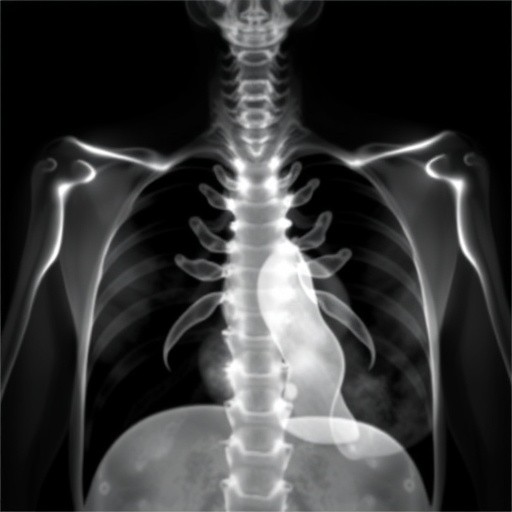

In recent years, the medical research community has long acknowledged a troubling disparity in neonatal outcomes: the male disadvantage in bronchopulmonary dysplasia (BPD). This chronic lung condition, primarily afflicting premature infants who require oxygen therapy or mechanical ventilation, has been consistently linked with worse prognoses for male newborns compared to females. However, the newest study published by Dassios and Roehr, titled “Reconsidering the male disadvantage in bronchopulmonary dysplasia: three exceptions,” challenges this prevailing narrative by meticulously dissecting instances where the typical gender-related vulnerability is not observed. This groundbreaking work compels a reassessment of gender biases in neonatal pulmonary biology and paves the way for more nuanced therapeutic approaches.

Classically, bronchopulmonary dysplasia develops as a multifactorial pathology where the interplay of premature birth, mechanical ventilation, oxygen toxicity, and inflammation culminates in disrupted alveolar and vascular development. Male infants have repeatedly been reported to experience more severe disease progression, attributed to factors such as delayed lung maturation, hormonal influences, and differing immune responses. However, Dassios and Roehr’s exploration suggests that these patterns are not universally applicable, as they identify three distinct clinical and biological contexts in which female infants may instead bear equal or greater susceptibility to BPD-related complications.